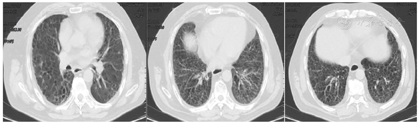

患者,男性,61岁,因"活动后憋气伴咳嗽半年余,胸痛5 d"入院。患者半年前(2019年11月)受凉后出现胸闷、憋气,活动后为著,伴咳嗽,无痰,休息后症状可缓解,就诊于我院,行胸部CT示肺间质纤维化,右肺下叶团片影(图1),予以抗感染、止咳、平喘等治疗。患者拒绝进一步检查明确右肺下叶团片影性质,后症状好转,准予出院。5天前(2020年4月16日)受凉后出现胸痛,深呼吸时加重,仍有活动后胸闷憋气,伴咳嗽,夜间可平卧入睡。患者自发病以来,饮食、睡眠尚可,大小便正常,近期体重无明显改变。患者既往有肺间质纤维化、干燥综合征、高血压等病史,无吸烟史。

2020年4月21日胸部CT平扫(图2):1.双肺间质纤维化合并感染,建议治疗后复查;2.右肺下叶团片影,较前2020年1月27日CT片范围增大,肺癌不能除外,建议穿刺活检;3.右肺门及纵隔肿大淋巴结较前增大;4.主动脉壁硬化;5.双侧胸膜肥厚;6.脂肪肝。2020年4月27日浅表包块彩色多普勒超声:双侧锁骨上区淋巴结肿大,建议必要时超声引导下穿刺活检。于2020年4月27日在超声引导下右侧锁骨上淋巴结穿刺活检术。2020年4月28日病理回报:(右颈部淋巴结)灰白穿刺组织3条,长均0.8 cm,直径均0.1 cm。病理诊断:(右颈部淋巴结穿刺组织)穿刺组织中见淋巴组织、坏死及异型细胞团,诊断为鳞状细胞癌转移。基因检测:EGFR(-),PD-L1 TPS 78%。